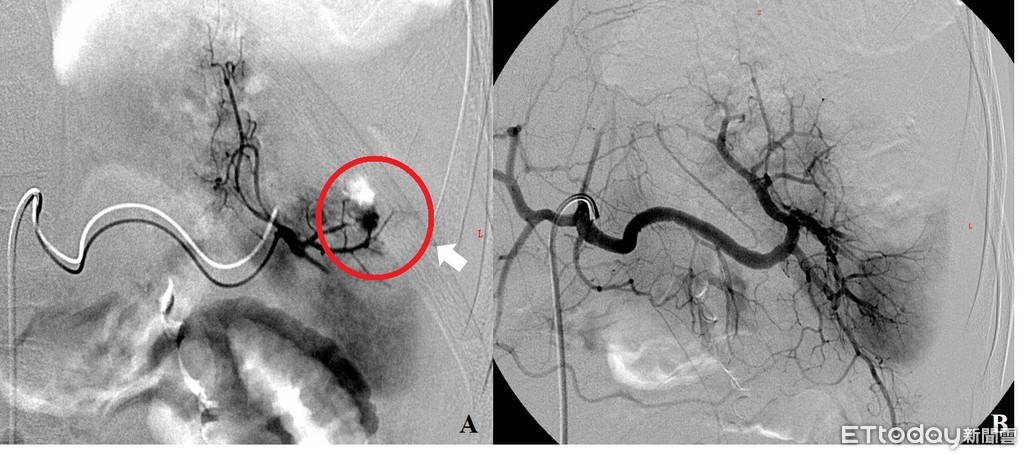

▲男童送醫時,可明顯看出血點(左圖),經血管栓塞治療後已無明顯出血點。(圖/記者許宥孺翻攝)

大同醫院胸腔外科醫師李彥龍指出,男童尚未發育完全,加上脾臟是人體免疫器官,如果摘除的話,可能影響男童未來的抵抗力,經手醫師採用血管栓塞止血治療,再輸血近千c.c.治療。